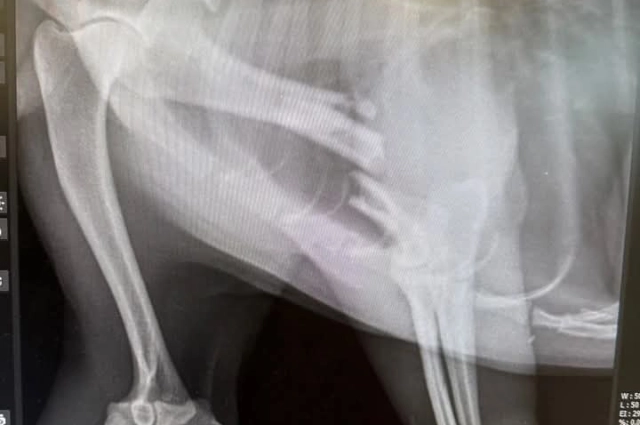

9. Förderung Tierarztpraxis ohne Grenzen gUG und Dr. K. Wontorra